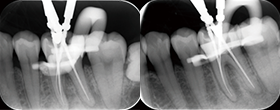

Case1 湾曲根管

• CC「左下奥違和感」主訴に来院

• 左下⑤6⑦Br除去→左下7 2次カリエス認める

• 湾曲大きく穿通せず…ハンドファイルで治療回数5回

EdgeSequel

Sapphire™#15/.06テーパーにてグライドパス形成

• 作業長確認

最終拡大#40/.04テーパー

Case2 直線根管

左下6遠心根に透過像認める

• インレー除去

透過像に一致した部位にサイナストラクト認める

• コンポジットレジンにて隔壁作成

最終拡大#30/.04テーパー